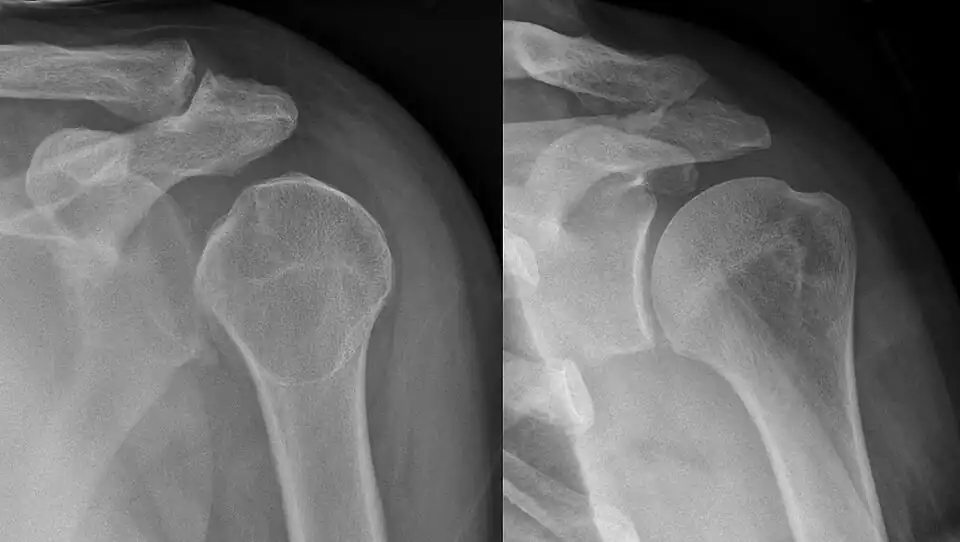

Shoulder dislocation before (left) and after (right) being reduced -